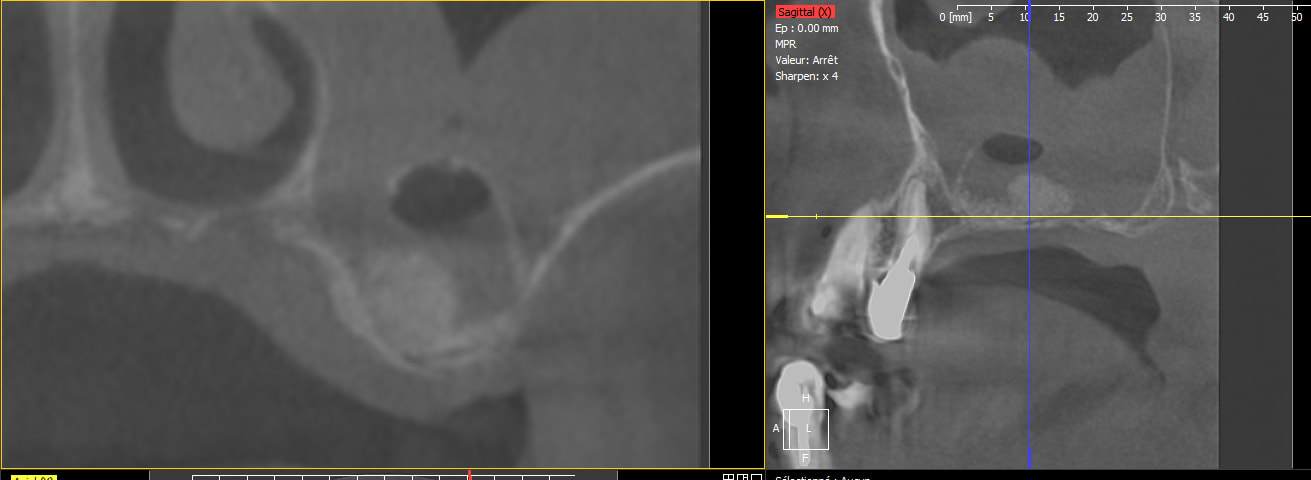

Pano apres la chir secteur 2,

puis cbct a 8jours car douleur persistante,

perfo secondaire ou pbleme infectieux??

Je ne suis pas specialiste en elevation mais la lacune qui est apparue au sein du materiau me semble etonante ; l'epaississement dela membrane etait il preexistant ?

Il y avait déjà une pathologie existante peut-être non? Mais en effet, on dirait que ton biomat a migré en palatin. Ouvre à nouveau, aspire tout ce que tu peux et regarde si l'inflammation régresse. Tiens-nous au courant stp et courage pour la suite.

greffe qui s'est infetée, la lacune provient de gaz fomés dans ton biomat par des bactéries. début de la merde qui commence. moi j'ouvre dès que possible, je nettoye au max et irrigue ++++à la betadine, sous augmentin.